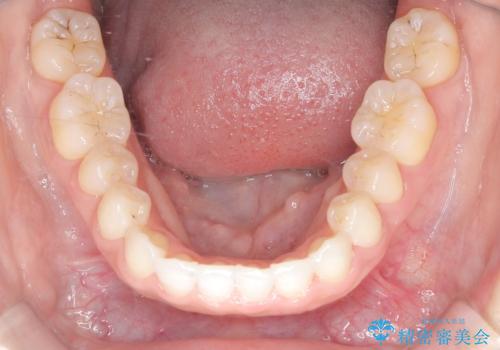

- 前歯の凸凹を主訴に来院された患者様です。

カウンセリング時に、側切歯が矮小歯であることを指摘したところ、適切な幅径での修復を希望されました。

インビザラインを用い、計画通りに歯並びを改善することができました。

矮小歯の幅径を大きくすることで、より理想的な噛み合わせを作ることができます。